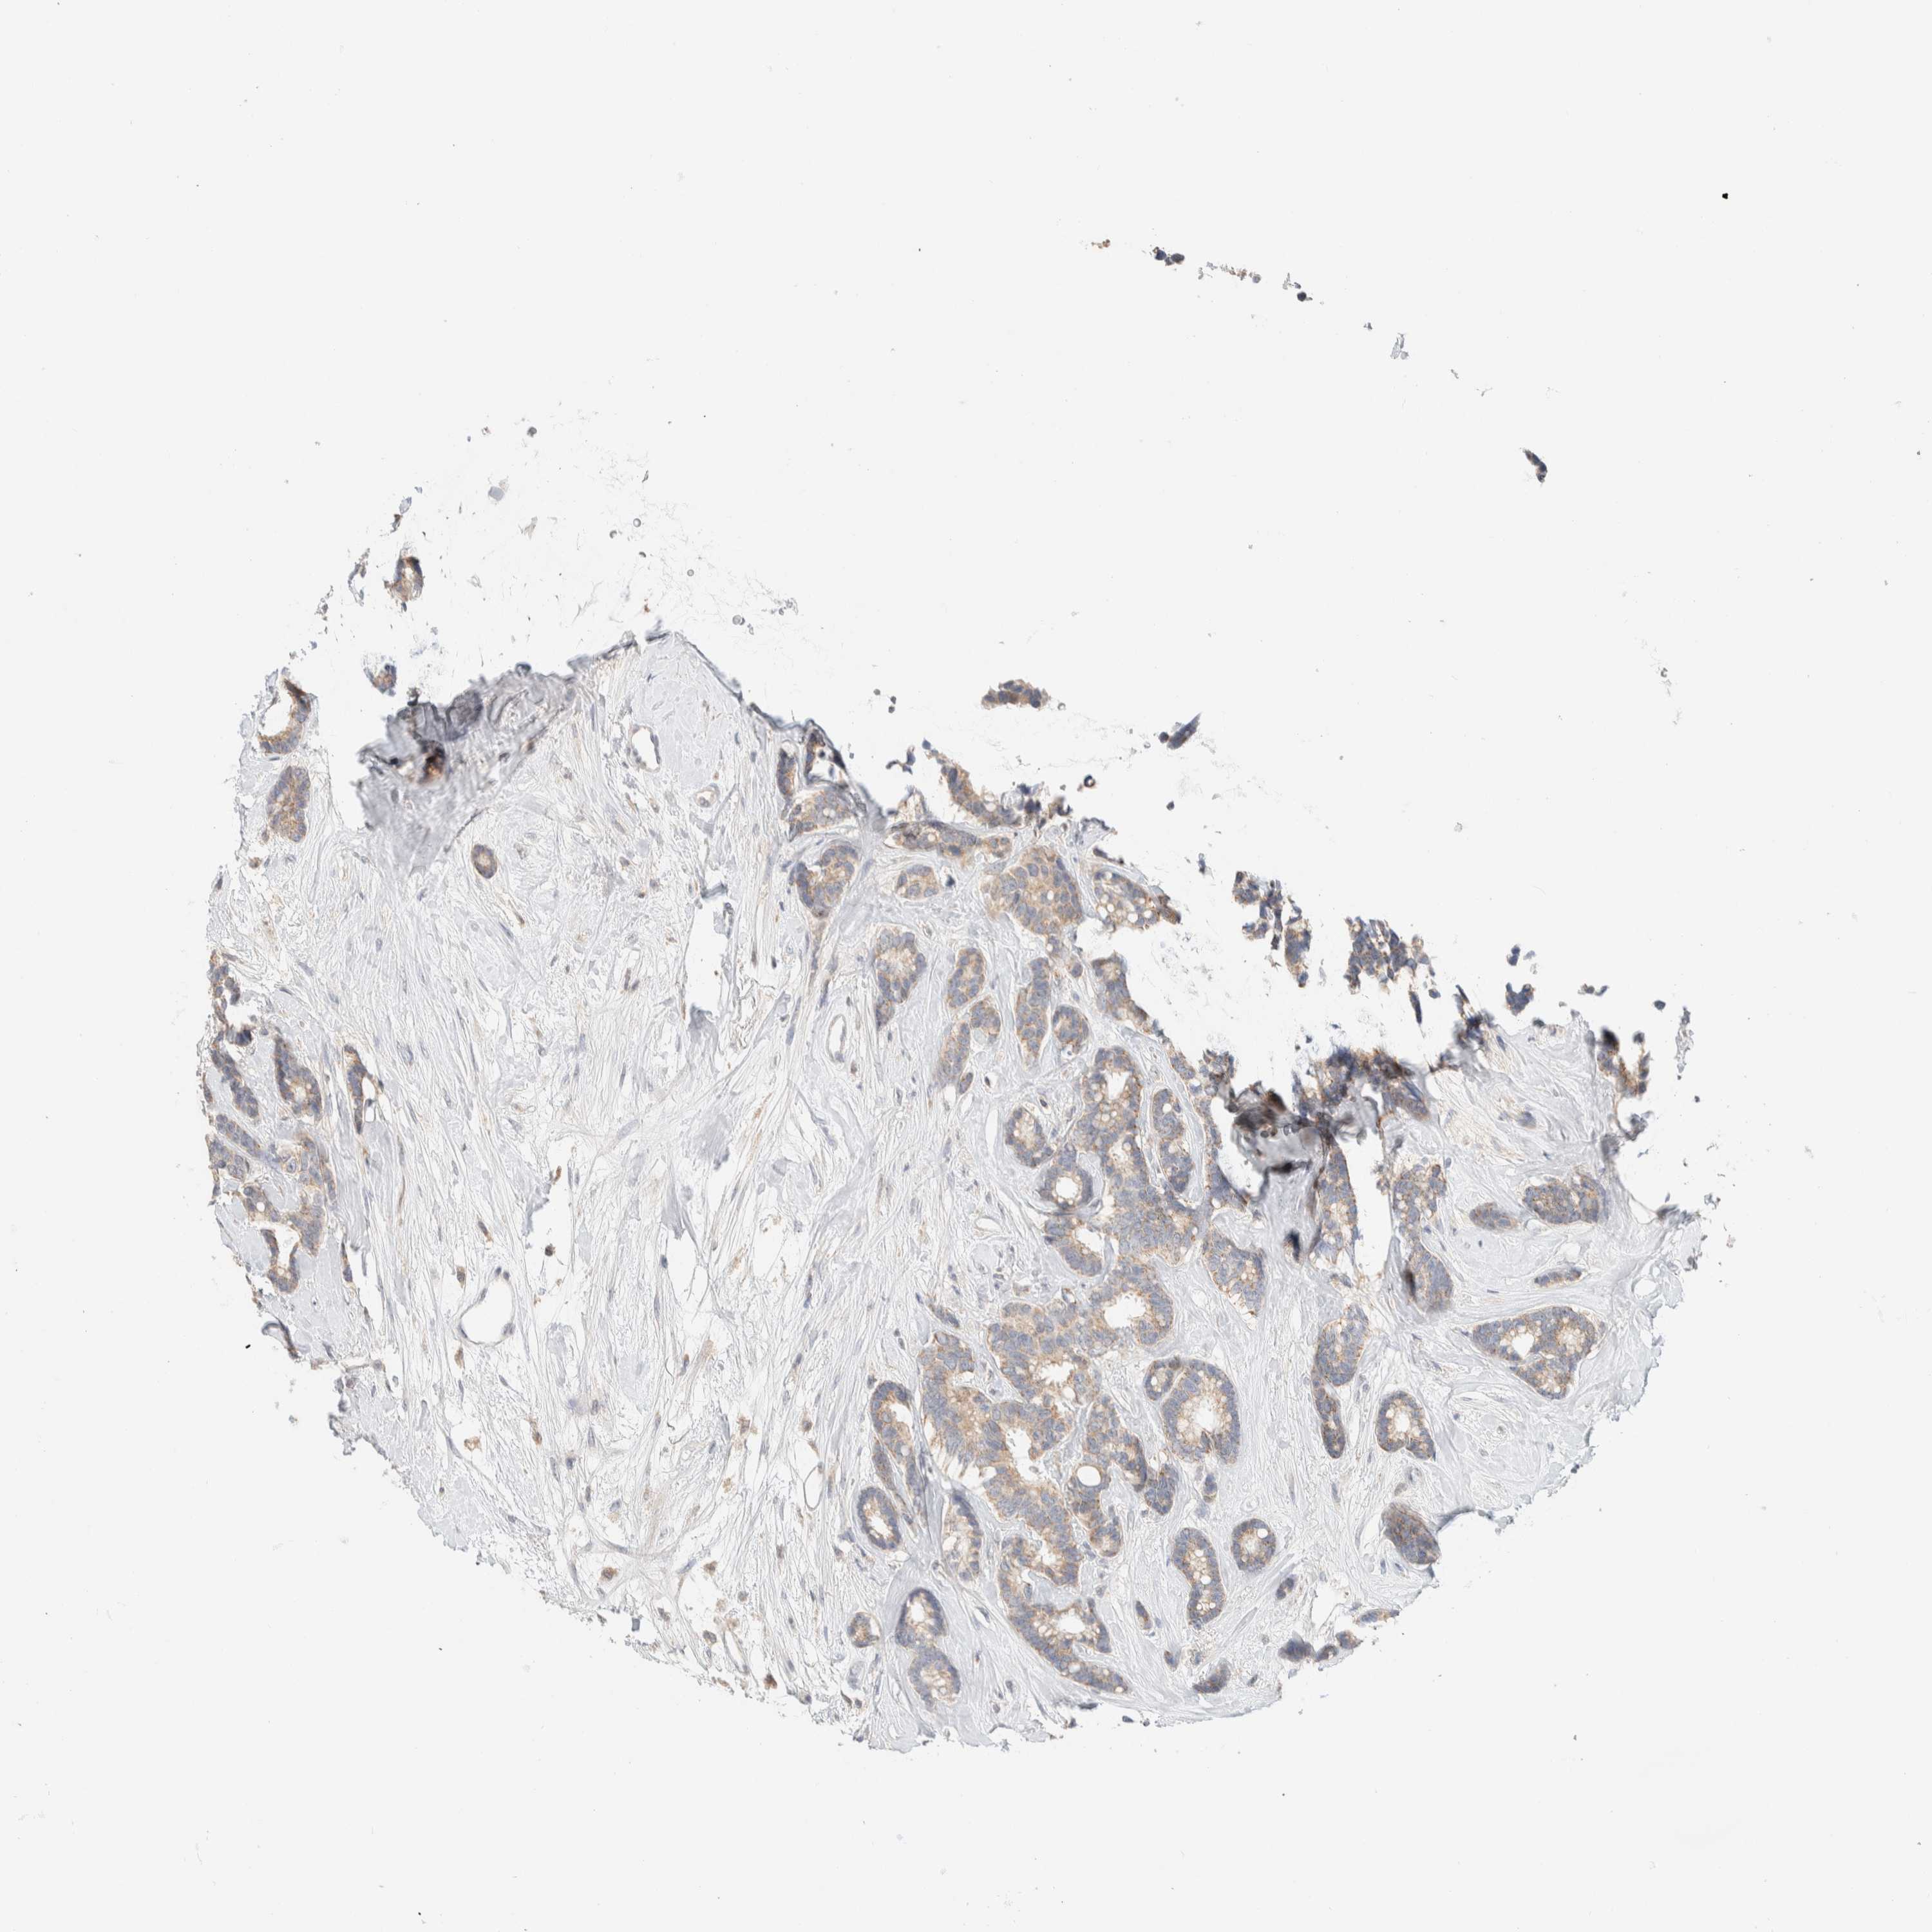

CANCER BREAST CANCER Show tissue menu

BRCA TCGA BRCA VALIDATION PROTEIN EXPRESSION